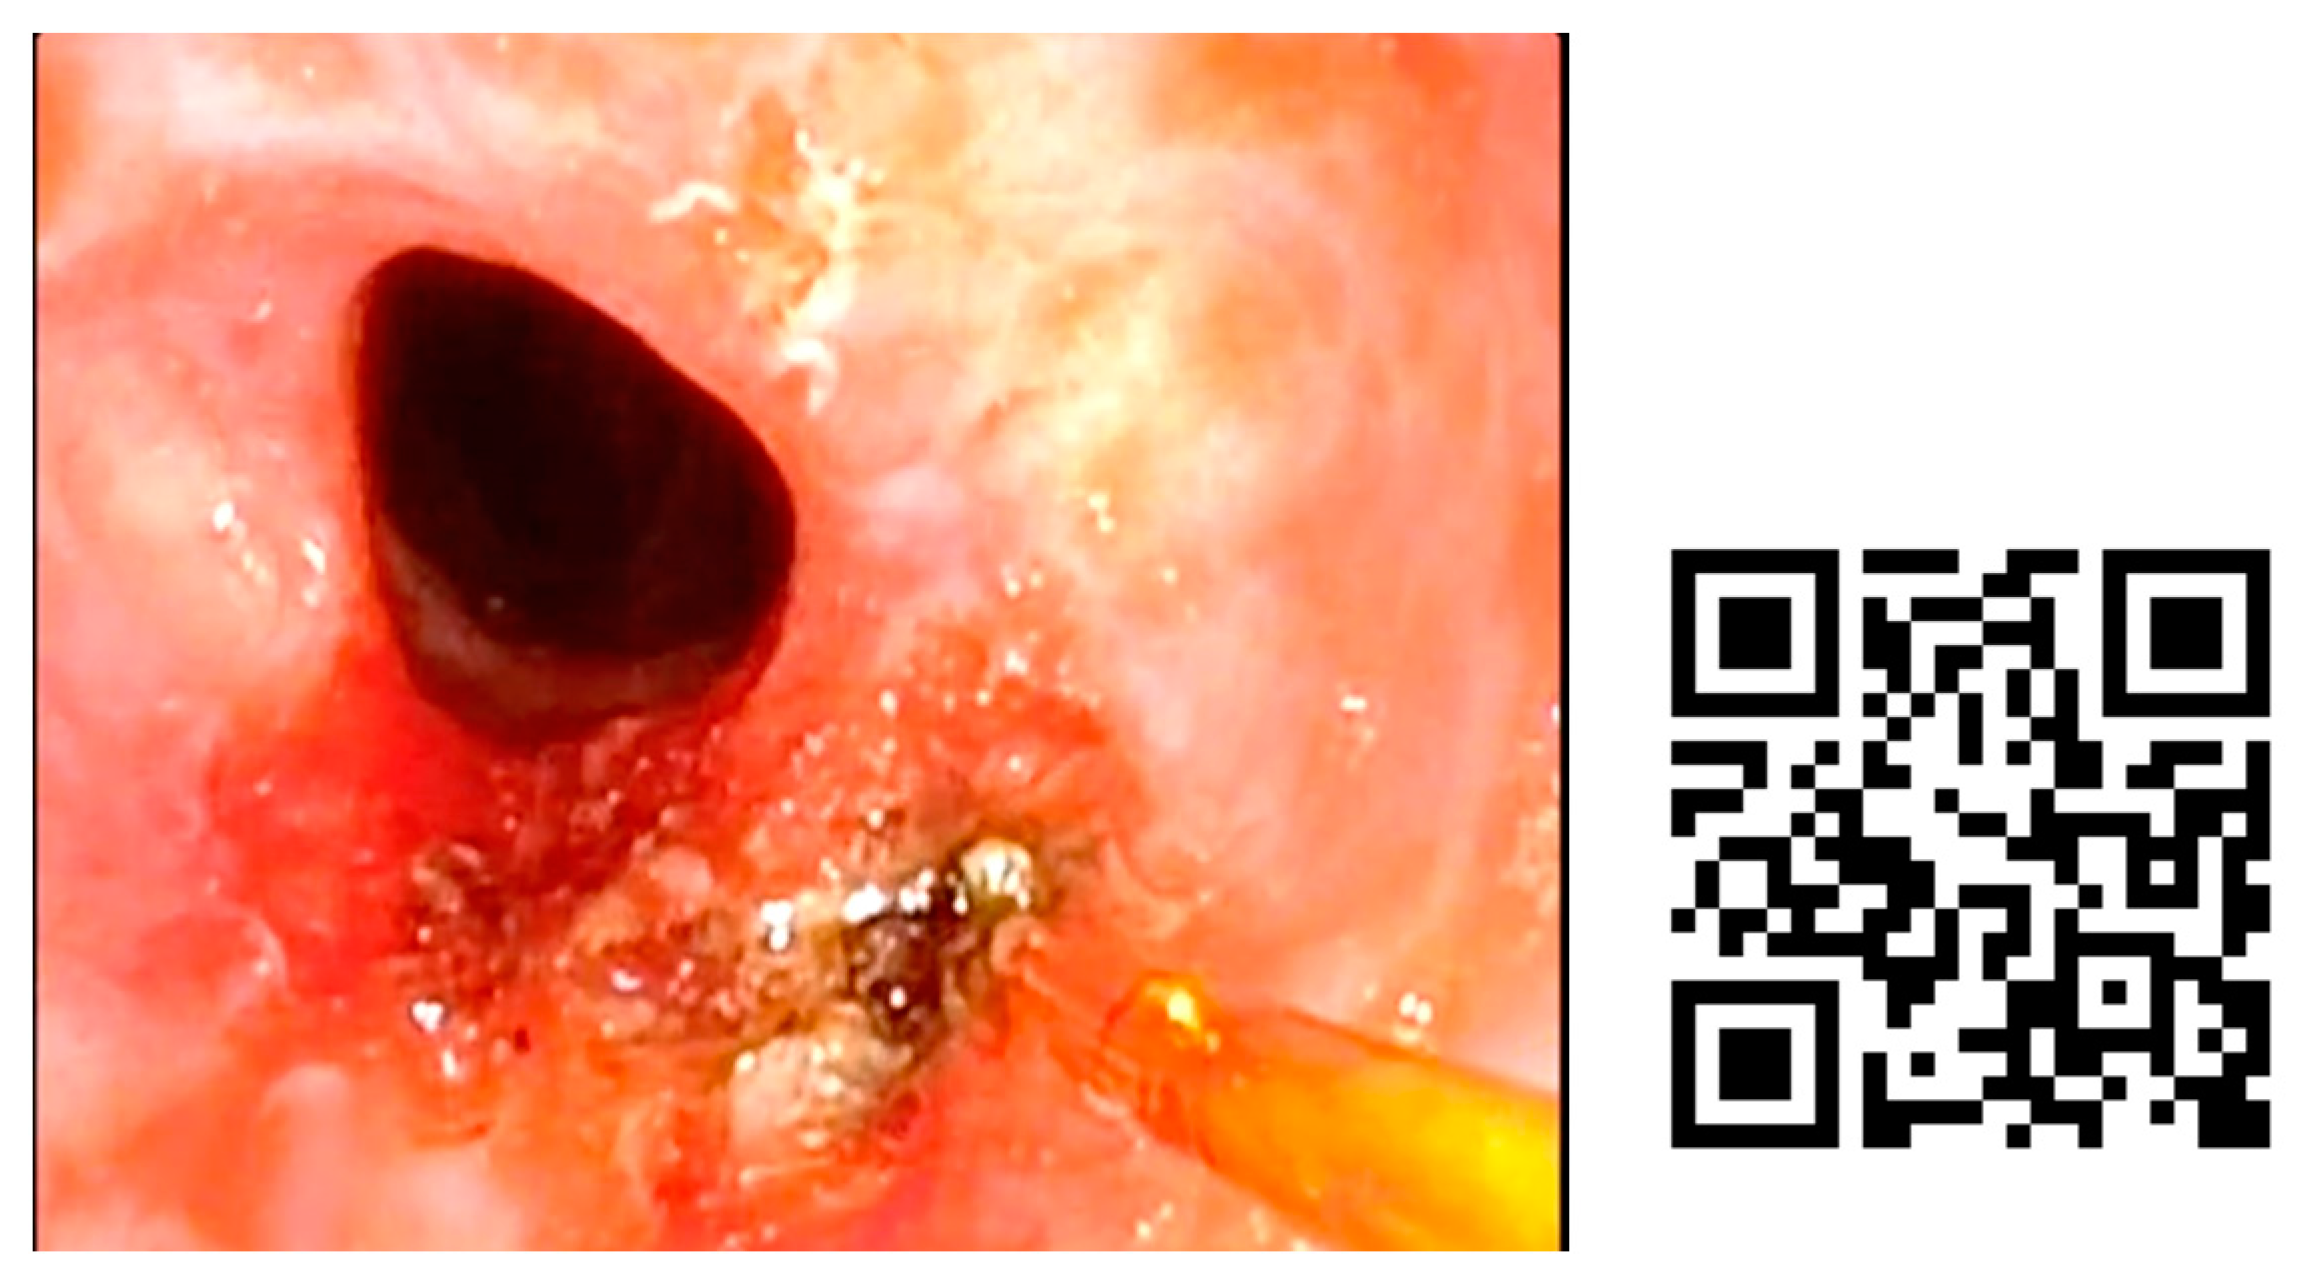

In Figure 4, we present an example of subglottic stenosis after a long intubation in the ICU. The patient always remained stable and blue laser treatment was performed in the office.

Figure 4. Subglottic stenosis treated by blue laser in ENT office. She was diagnosed after presenting to the emergency department for progressive dyspnea of 10 days’ evolution. As a relevant history, the patient had been admitted to the ICU for 30 days, 15 days with orotracheal intubation. Fibroscopy examination was performed to diagnose the stenosis. After anesthetizing the larynx by subglottic infiltration of local anesthetic, a channel videofibroscope was used and a 400 nm fiber was employed to perform radial resection of the subglottic stenosis, without further topical treatment.